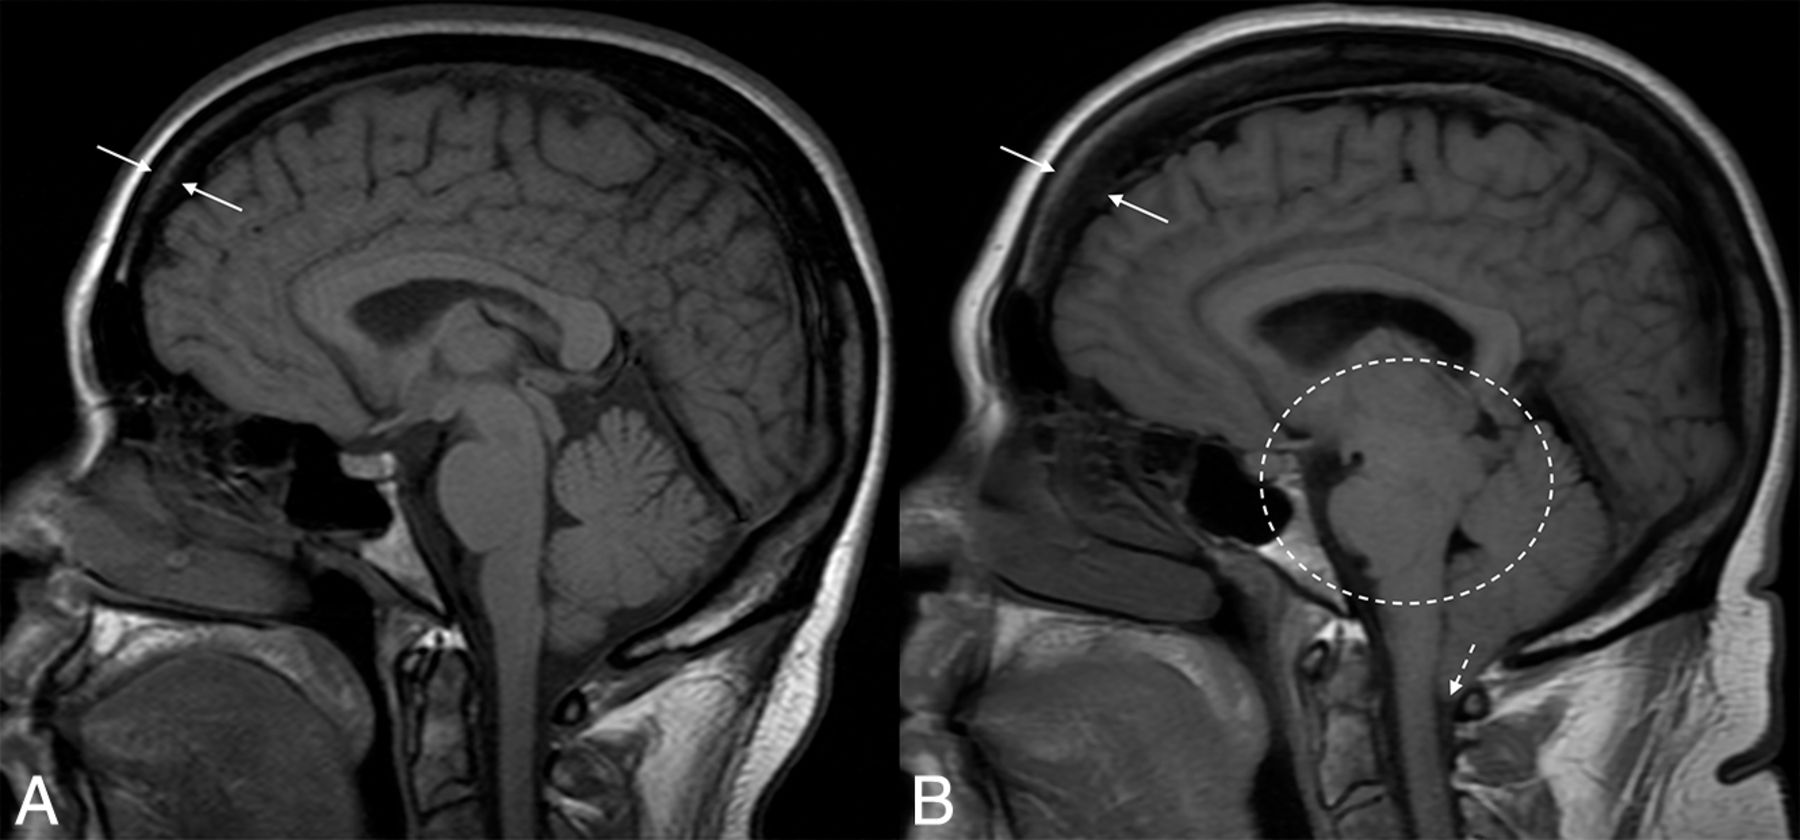

Hyperostosis related to a CSF leak. Sagittal T1-weight images before (A) and after (B) the development and diagnosis of SIH, with 16 years between examinations. Multiple classic findings of SIH are seen, including brain sag (dashed oval) and herniation of the cerebellar tonsils through the foramen magnum (dashed arrow). The patient also developed substantial frontal-predominant calvarial hyperostosis (between solid arrows), particularly along the inner table of the skull.